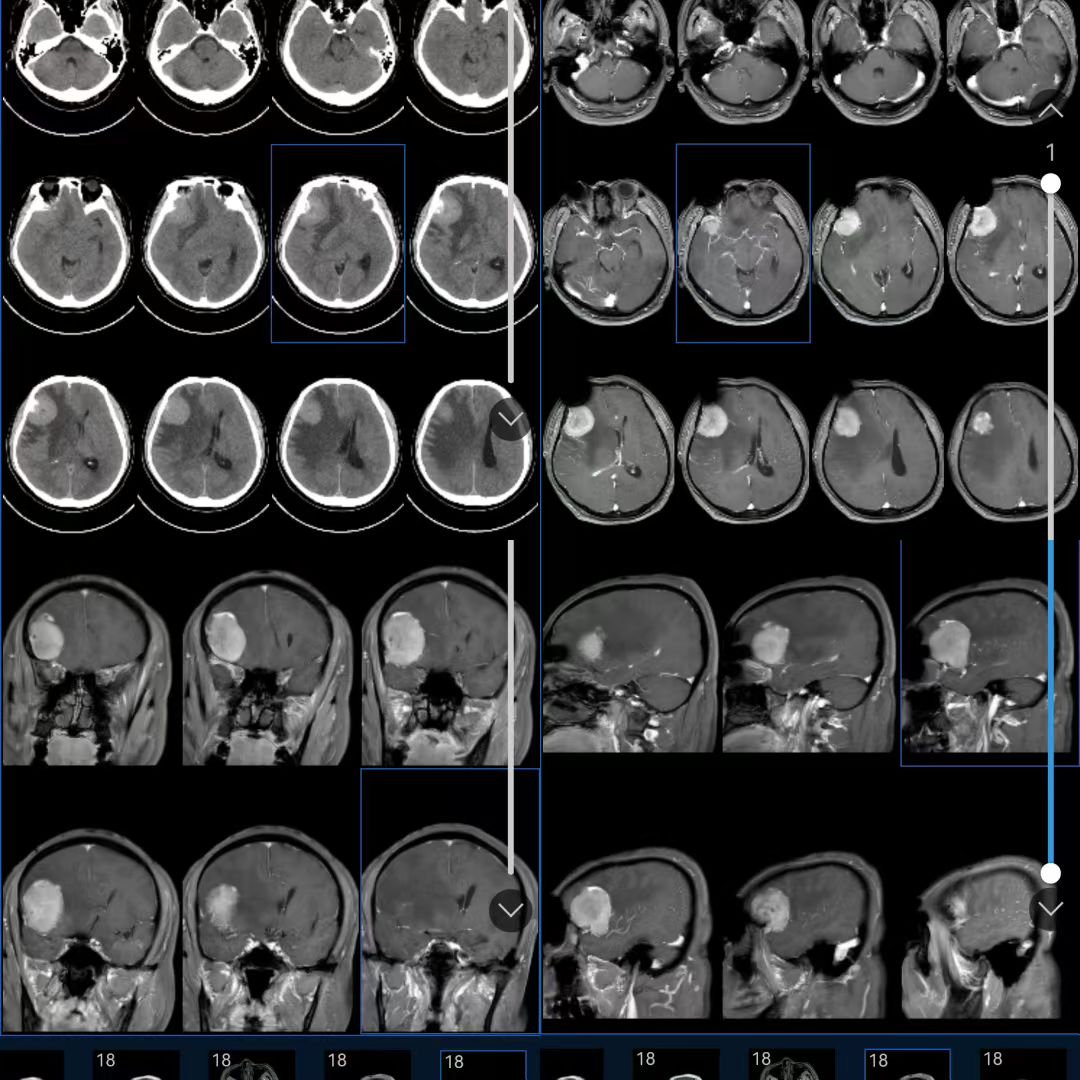

CT检查结果让大家心头一紧,佟先生右侧额叶存在一个直径44mm的巨大脑膜瘤,这个瘤体已经压迫到了脑组织,还导致瘤体周围出现了严重水肿。更让人担忧的是,磁共振检查进一步提示,这个脑膜瘤血供丰富,而且在同侧大脑中动脉竟然还存在一个动脉瘤,这就好比在一个“炸弹”旁边又埋下了一个“炸弹”,随时可能危及生命。

术前CT及核磁